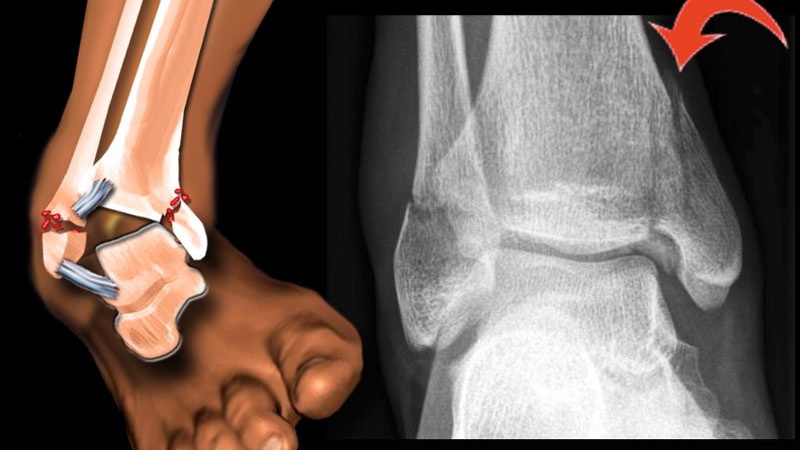

Gãy xương cẳng chân là tình trạng gãy một hoặc cả hai xương cẳng chân, từ mâm chày đến mắt cá chân. Có nhiều cách phân loại kiểu gãy xương cẳng chân, cụ thể: